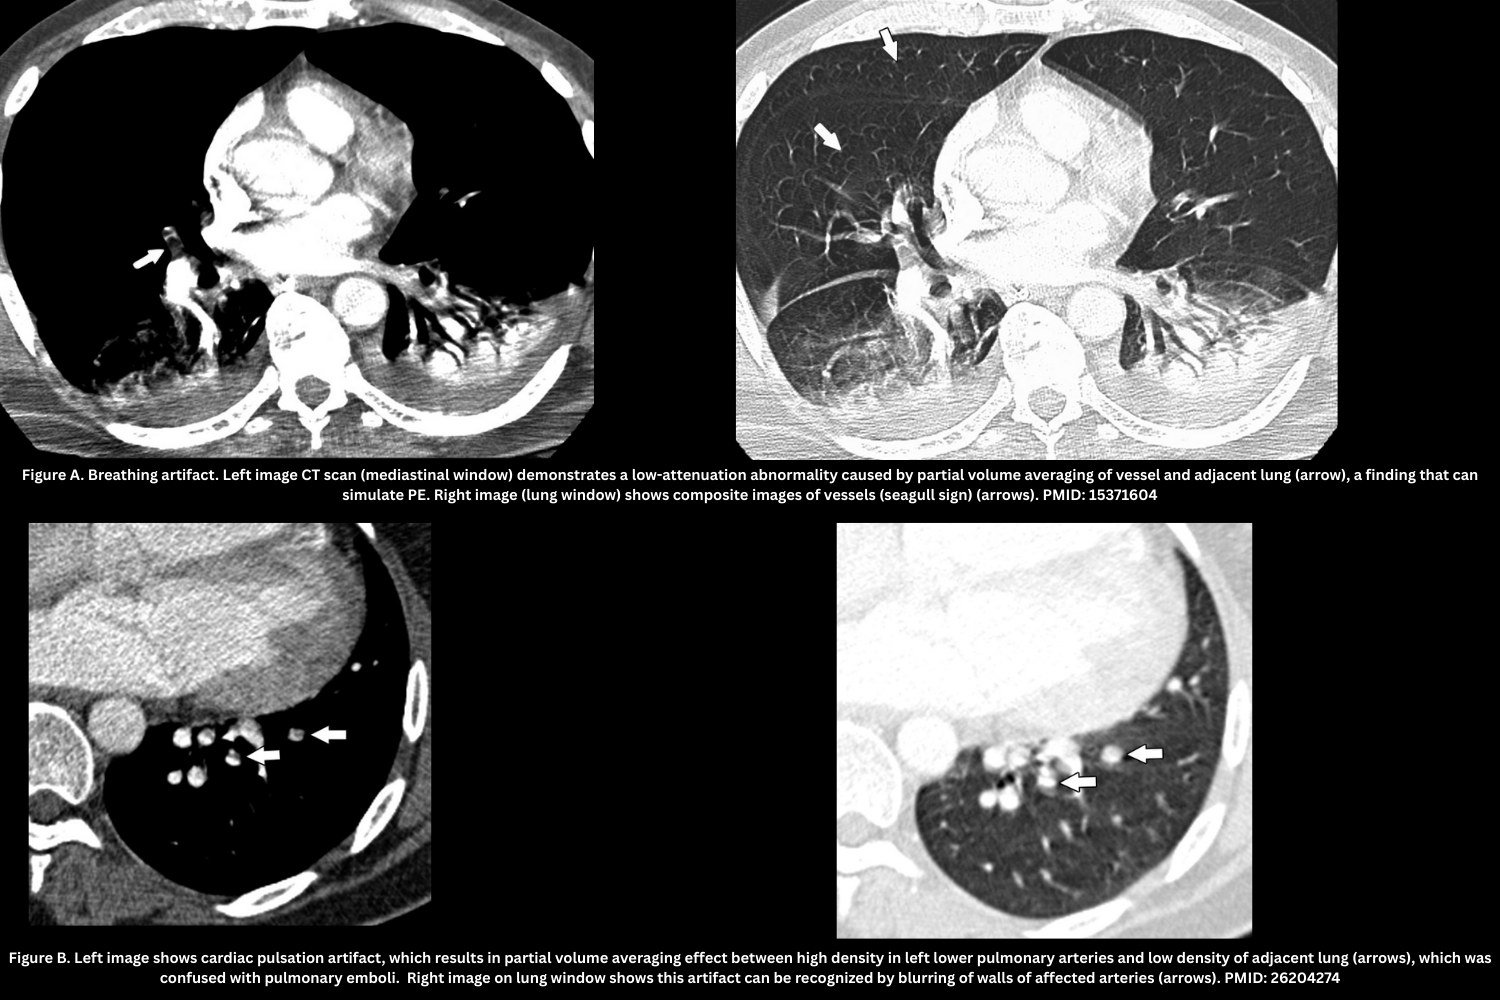

Patient-Related Artifacts

- Motion artifact (breathing artifact, cardiac pulsation artifact). Figure A, B.

- Blurring, “seagull sign,” shifting vessel position across slices.

- Best seen on lung windows.

- Leads to an indeterminate diagnosis at that level.

- Flow-related artifact (transient interruption of contrast). Figure C.

- Poor mixing of contrast/unopacified blood → patchy low attenuation in lower lobe arteries.

- Appearance: Filling defect with poorly-defined margins from mixing of opacified and unopacified blood (“transient interruption of contrast”), attenuation >78 HU.

- Caused by deep inspiration or IVC inflow; reduced with mild inspiration or apnea coaching.

Technical Artifacts

- Beam-Hardening Artifact (Figure D)

- Appearance: Dense streaks from high-density structures (e.g., pooled contrast agent in the right atrium, SVC or other adjacent vessels, metallic structures such as pacemakers, or the patient’s arms if they cannot be elevated above the chest), often projecting over the right pulmonary artery or medial upper lobe vessels.

- Pearl: Use a saline chaser and optimized bolus protocols to reduce SVC streaking.

- Partial volume artifact (Figure E)

- Thick slices/axial orientation cause blurred low-attenuation defects.

- Partial volume artifact is caused by the CT system averaging varying tissue densities within a single voxel, leading to blurred edges or incorrect CT numbers at tissue interfaces

- Not reproducible on contiguous slices.

- Stair-step artifact (Figure F)

- The stair-step artifact consists of low-attenuation lines seen traversing a vessel on coronal and sagittal reformatted images and is accentuated by cardiac and respiratory motion.

- Reduced with overlapping reconstructions.